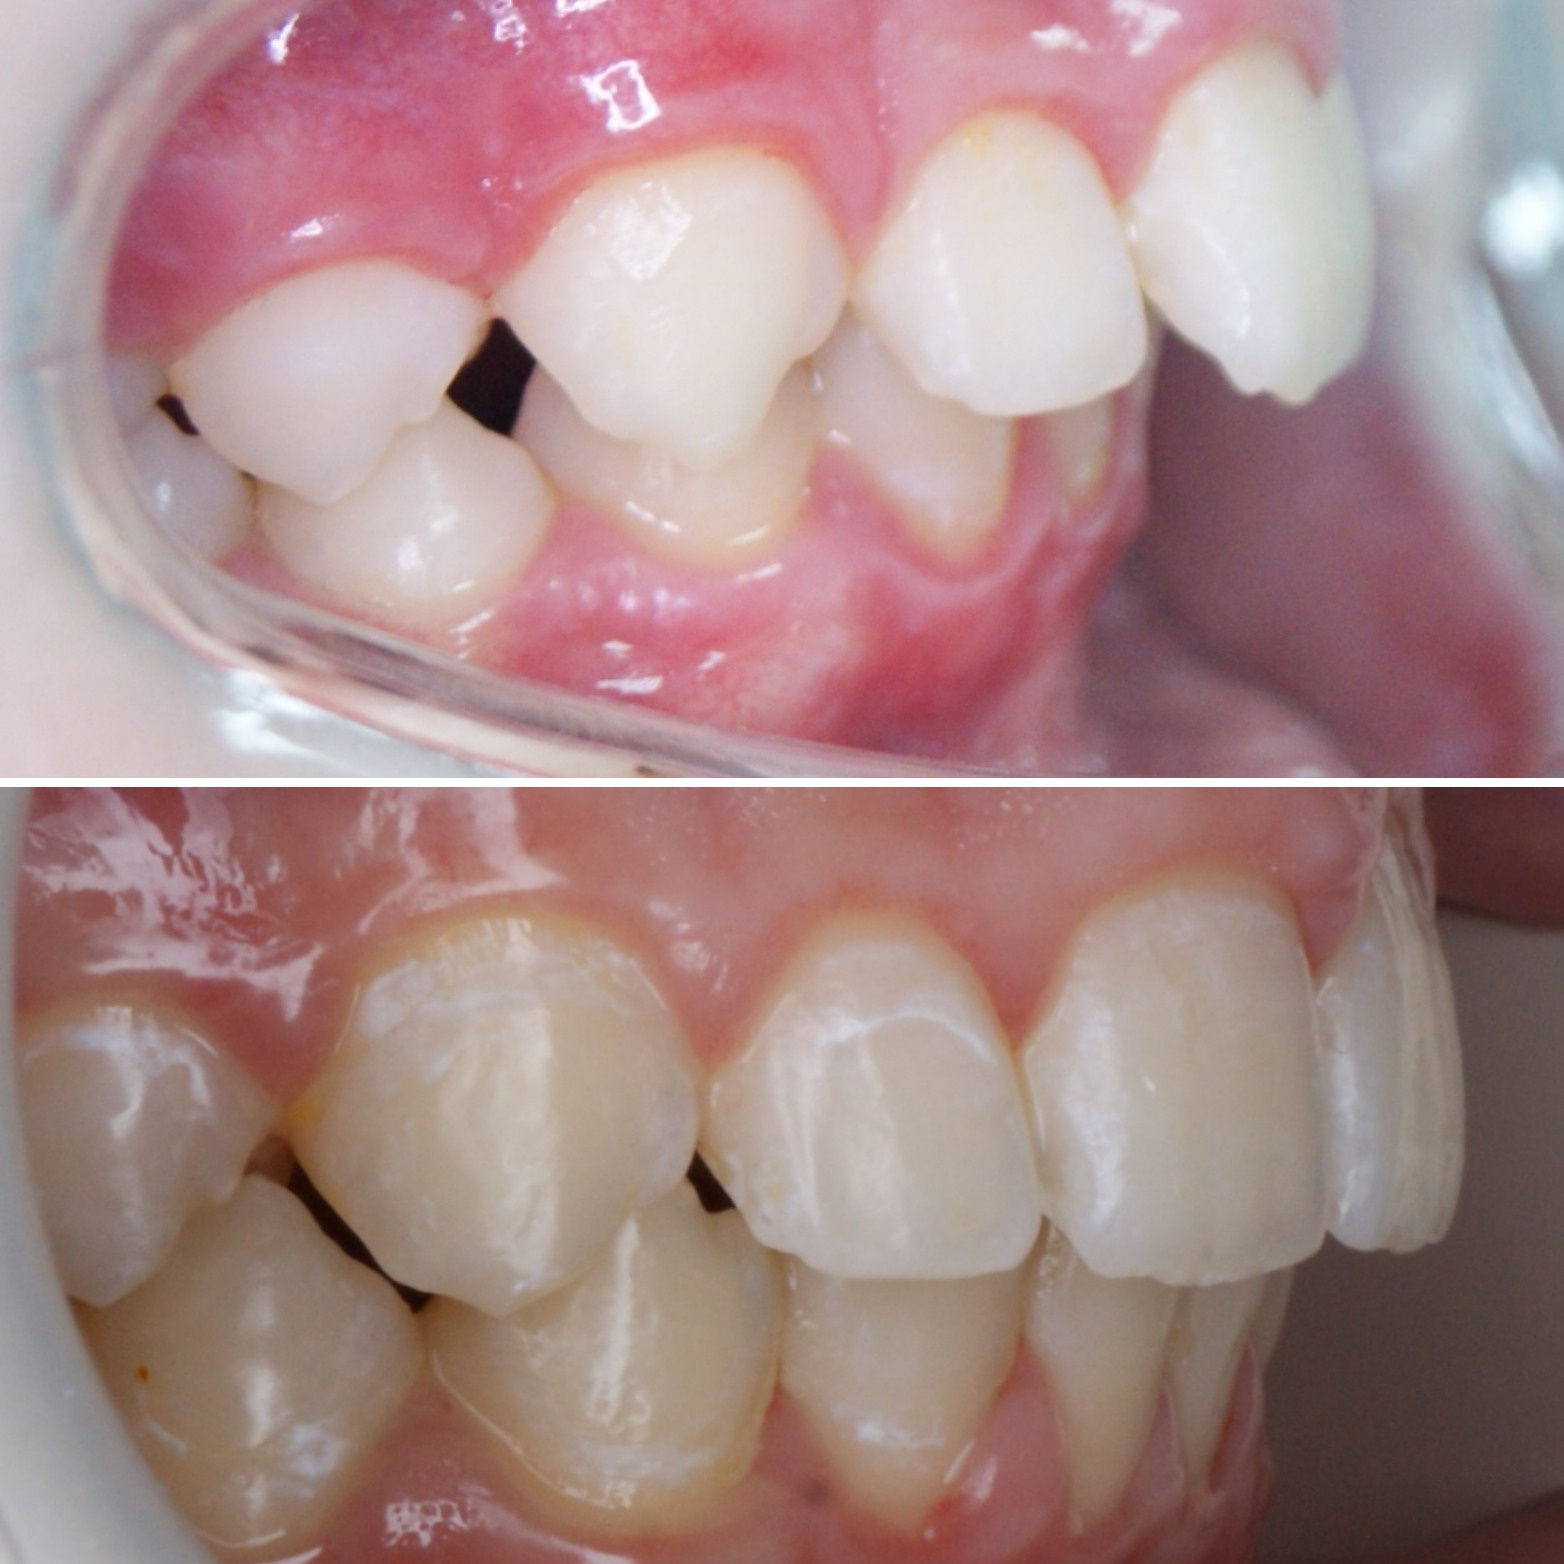

🔷️ Промежуточный результат лечения на аппарате Марко Роса (6 месяцев). Пациенту 7 лет. Самое удивительное - как "отвечает" на лечение нижняя челюсть: расширяется, меняется её положение и корректируется дистальный прикус, выравниваются нижние зубы, хотя никаких аппаратов на нижней челюсти не было!

P.S. Каждый случай уникальный, чаще нижнюю челюсть мы всё таки расширяем тоже.